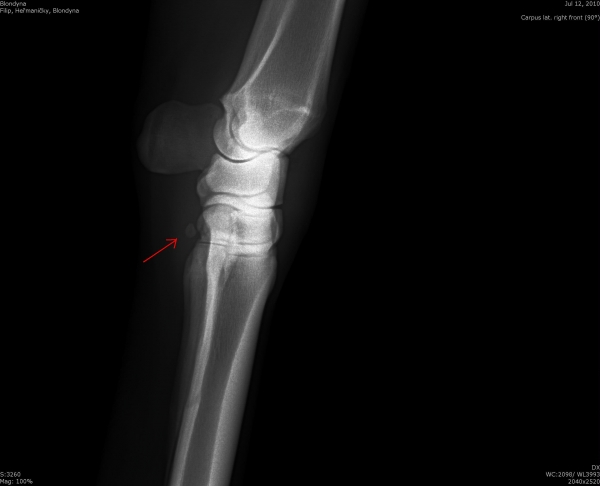

Ankylóza spěnkovýho kloubu

rentgenologické vyšetření

Těžká artróza ve spěnkovém kloubu